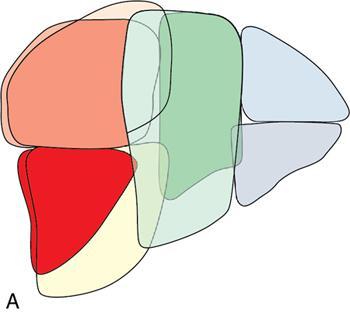

Ritu K. Kashikar, Shrinivas B. Desai Imaging is the mainstay of noninvasive diagnosis of the spectrum of abdominal pathologies or proving absence off thereof. Knowledge of normal anatomy and important normal variants is thus essential for the radiologist in order to avoid misinterpretation or erroneous diagnosis. This chapter highlights the normal anatomy of the hepatobiliary systems including the blood vessel and draining ducts and discusses relevant anatomical variants which may have important clinic implications. The liver is the largest abdominal organ, occupying the right upper abdominal quadrant and is in close approximation with the diaphragm, stomach and the gallbladder. It is largely covered by the costal cartilages. The liver is encapsulated by Glisson’s capsule which is a dense layer of connective tissue. It is covered by peritoneum, except in the regions of gallbladder fossa, fossa for inferior vena cava (IVC), and the bare area. The bare area is the posterocranial aspect of the liver, adjacent to the dorsal body wall, which is not covered by peritoneum. The liver has two surfaces, the convex diaphragmatic surface and a concave visceral surface. The slit in the hepatic hilum is called the porta hepatis and is penetrated by the right and left hepatic ducts (LHDs), hepatic artery and portal vein (PV). The distal portion of the lesser omentum is called the hepatoduodenal ligament and contains the common bile duct (CBD), hepatic artery, PV, nerves of liver and lymphatics. The liver has dual blood supply with hepatic artery providing 25% of hepatic blood and rest by portal vein (Fig. 9.2.1). Five ligaments connect the liver to the undersurface of the diaphragm. These include the falciform, the coronary and two lateral ligaments, all of which are peritoneal folds. The fifth ligament is a fibrous cord-like structure and represents the obliterated umbilical vein. The peritoneum invaginates into the liver parenchyma leading to formation of fissures. There are four normal fissures: fissures for the ligamentum teres, ligamentum venosum and gallbladder and the transverse fissure (Fig. 9.2.2). The liver is organized into microscopic functional units called lobules or acini. A central terminal hepatic venule surrounded by four to six terminal portal triads form a polygonal unit called the hepatic lobule. The terminal portal triad branches line the periphery of the unit. Between the terminal portal triads and the central hepatic venule the hepatocytes are arranged in one cell thick plates, surrounded by sinusoids. The blood flows from the terminal portal triad through sinusoids into terminal hepatic venule. Bile formed within the hepatocytes empties into terminal canaliculi which coalesce into the bile ducts (Fig. 9.2.3). This structure of the functional hepatic unit forms the basis of various functions of the liver. The normal relations of the liver are: The liver can be divided into right, left and caudate lobes. The right and left lobes are separated by the interlobular fissure and is oriented along a line passing through the gallbladder fossa inferiorly and the middle hepatic vein (MHV) superiorly (Fig. 9.2.4). This plane runs from the left of the IVC to the left of the gallbladder fossa and is a called the Cantlie’s line. Use of standardized, segmental anatomy is imperative because it facilitates communication and treatment planning. The segmental anatomy of liver is primarily based on vascular anatomy. The right lobe is divided into anterior and posterior sectors by of the right hepatic vein (RHV). The left lobe is divided into medial and lateraI sectors by an oblique plane connecting the left hepatic vein (LHV) and the falciform ligament. The liver is divided into upper and lower segments at the level of main portal vein (MPV) bifurcation (Fig. 9.2.5). Various systems are used in classification of liver anatomy. These are discussed in Table 9.2.1. The Couinaud’s system is the most commonly used and divides eight sections/segments which are discussed in details below (Table 9.2.2). 1. Segment 1 – Caudate lobe Bounded anteriorly and medially by the fissure for ligamentum venosum (Fig. 9.2.6). 2. Segment 2: Superior segment of the left lateral sector/section Bounded medially by falciform ligament and inferiorly by plane of MPV, also known as the posterior lateral sector (Bismuth, FCAT) (Fig. 9.2.7). 3. Segment 3: Inferior segment of left lateral sector/section Bounded medially by the falciform ligament and superiorly by the plane of the MPV bifurcation, also referred to as lateral anterior sector (Bismuth, FCAT) (Fig. 9.2.8). 4. Segment 4: Left medial sector/section Bounded laterally by falciform ligament and medially by Cantlie’s line (Fig. 9.2.9). 5. Segment 5: Inferior segment of the right anterior sector/section Bounded anteriorly by the gallbladder fossa and posteriorly by the plane of the RHV, superiorly bounded by the plane of MPV bifurcation (Fig. 9.2.10). 6. Segment 6: Inferior segment of the right posterior sector/section Bounded anteriorly by plane of the RHP and superiorly by the plane of the MPV bifurcation (Fig. 9.2.11). 7. Segment 7: Superior segment of the right posterior sector/section Bounded anteriorly by the plane of the RHV and inferiorly by the plane of the MPV bifurcation (Fig. 9.2.12). 8. Segment 8: Superior segment of the right anterior sector/section Bounded anteriorly by the plane of the gallbladder fossa and MHV, posteriorly bounded by the plane of the RHV and inferiorly by the plane of the MPV bifurcation (Fig. 9.2.13). Owing to its broad area of contact with the anterior abdominal wall, the liver is an ideal organ for evaluation with sonography. Ultrasound is commonly used for evaluation of size of the liver. On longitudinal scans obtained through the midhepatic line, if the liver measures 13 cm or less, it is normal in 93% of individuals (Fig. 9.2.14). The size of liver in various planes is discussed in chapter on normograms. When the area of contact between the liver and the anterior border of the right kidney, exceeds below two thirds of the kidney, the liver is considered as enlarged. The normal liver is homogeneous with fine echoes and appears evenly bright. The hepatic veins, PV and fissures interrupt the homogeneity of the liver parenchyma (Fig. 9.2.15). The parenchymal echogenicity may vary depending on the equipment, transducer and gain settings and should be judged by comparison with internal references like right renal cortex, body of the pancreas and PV walls. When compared with the adjacent normal right renal cortex the liver normally appears hyperechoic or isoechoic. The pancreas in a young individual is hypoechoic compared to the liver, and isoechoic in middle aged adults. As age progresses and fatty infiltration of the pancreas occurs, the pancreas appears hyperechoic to the liver. The liver is hypoechoic to the spleen. The normal liver reveals a density of 55–65 HU on nonenhanced scan and should appear homogenous with the exception of hypodensity in the regions of vessels and fissures. The liver parenchymal enhancement is minimal the arterial phase, with increase in density by only approximately 10 HU. This phase is usually to access vascular anatomy and to detect neovascular enhancing lesion like HCC, metastasis. Considering the fact that 75% of heptic venous supply is from the PV, the normal hepatic parenchyma shows maximum enhancement in the portal venous phase. During the venous/delayed phase the hepatic attenuation starts falling (Fig. 9.2.16). The hepatic fissures appear as linear fat containing structures. All the four fissures are well identifies on CT (Figs. 9.2.17–9.2.20). Normal liver should demonstrate uniform T1 signal similar or isointense to the paraspinal muscles and slightly hyper intense to the spleen. No signal drop should be seen on in or opposite phase. On T2W1 images liver appears slightly hyperintense to paraspinal muscles, isointense to pancreas and hypointense to spleen (Fig. 9.2.21). Following administration of extracellular contrast agents the normal liver parenchyma enhances on PV phase similar to that seen on CT. The arterial phase is preserved to determining vascular anatomy, variants and tumoural enhancement. Gadoxetic acid (Eovist) and gadobenate dimeglumine (MultiHance) are hepatobiliary agents showing excretion by the liver. In the case of gadoxetic acid, hepatic excretion is ~50%, which allows imaging in the hepatobiliary phase at ~20 minutes following injection. Gadobenate has only 3%–5% biliary excretion with hepatobiliary phase at approximately 40 minutes (Fig. 9.2.22). This property makes these agents useful in detection of nonhepatocyte containing lesions which appear hypointense to background liver on hepatobiliary phase. Hepatic anatomic variants are relatively common and represent normal interindividual variation of liver morphology. Normal Anatomic Variants Anatomic anomalies Accessory and pseudofissures may be seen in the liver. True accessory fissures result from infolding of the peritoneum usually along the undersurface of the liver and are rare. The inferior accessory fissure is the commonest accessory fissure and divides the posterior segment of the right hepatic lobe into lateral and medial portions. Diaphragmatic slips may cause indentation over the liver surface and are not commonly seen on imaging (Fig. 9.2.23). Leftward extension of the lateral segment of the left hepatic lobe appearing as a crescentic density that wraps around the spleen is referred to as sliver of liver. The left lobe of the liver may exhibit various forms: leaf like; spatular; truncated pyramid/wedge shaped; and a bifid appearance (Fig. 9.2.24). Elongated left lobe may be mimic splenomegaly, perisplenic hypoechoic collections or less commonly tumours. Imaging clues to diagnosis are establishing contiguity with liver and visualization of parenchymal vessels coursing through. The portion of the liver that extends medially from the right lobe between the IVC and fissure for ligamentum venosum is called the caudate lobe. The caudate lobe is divided inferiorly into a lateral caudate process and a medial papillary process. The medial papillary process projects medially towards the pancreatic head and has applied importance (Fig. 9.2.25). Riedel’s lobe is a tongue-like projection from the anterior aspect of the right lobe and the most common accessory lobe of the liver. It is seen most frequently in asthenic women. The reported prevalence of RL, ranges from 3.3% to 14.5% and the prevalence is higher in women than in men. It can be 20 cm or more in length and may extend up to the iliac fossa. It is usually asymptomatic and is discovered incidentally (Fig. 9.2.26). Accessory liver lobes are defined as a supernumerary lobe of normal hepatic parenchyma in continuity with the liver. This is a rare entity and usually occurs as a result of congenital ectopic hepatic tissue, although rarely may occur as a result of trauma or surgery. Various systems are proposed for classification of ALL. Another method of classification has been proposed based on biliary drainage and presence or absence of capsule. Accessory lobes can be readily diagnosed and characterized on CT or magnetic resonance imaging (MRI) done for related or unrelated conditions. CT shows the lesion as a soft–tissue density mass attached to the liver and isodense to the organ. The portal/hepatic venous branches can be seen coursing through it, in contiguity with the liver (Fig. 9.2.27). The coeliac axis trifurcates into common hepatic, splenic and left gastric arteries at the level of T12–L1. The common hepatic artery becomes the proper hepatic artery after origin of the gastro-duodenal artery. The hepatic artery proper ascends anterior to the PV and medial to the CBD and divides in to right and left hepatic artery (LHA). Occasionally the middle hepatic (segment 4) artery arises from hepatic artery proper. The hepatic artery appears as a tubular hypoechoic structure and shows antegrade flow on Doppler (Fig. 9.2.28). Normally the resistive index is low ranging between 0.55 and 0.7. The hepatic artery, its anatomy, branches, course, calibre are best evaluated on arterial phase of dynamic CT (Fig. 9.2.29). This is also the preferred modality prior to hepatobiliary surgical planning. Contrast-enhanced MRI also shows the above details but spatial resolution is lower. Road map of the arterial vascularity of the donor and recipient is a prerequisite for transplant surgery and complex hepatobiliary surgery. Detailed hepatic arterial anatomy and its variations have its significance in liver surgeries and interventional hepatic procedures, relative to the hepatic lobe involved. A classification method was described by Michel et al. in 1955, and is discussed in Table 9.2.3 (Fig. 9.2.30). I: standard anatomy ~60% (range 55%–61%) II: replaced LHA ∼7.5% (range 3%–10%) III: replaced RHA ~10% (range 8%–11 %) IV: replaced RHA and LHA ~1% V: accessory LHA from LGA ~10% (range 8%–11%) VI: accessory RHA from SMA ~5% (range 1.5%–7%) VII: accessory RHA and LHA ~1% VIII: accessory RHA and LHA and replaced LHA or RHA ~2.5% IX: CHA replaced to SMA ~3% (range 2%–4.5%) X: CHA replaced to LGA ~0.5% Other unclassified variants are: The two most common variants are the replaced right hepatic artery (RHA) arising from the SMA (Fig. 9.2.31) and replaced LHA arising from the left gastric artery (Figs. 9.2.32–9.2.34). Segment 4 artery – Middle hepatic artery (MHA) The middle hepatic artery usually arises from the LHA, it may, however, arise from the RHA (Fig. 9.2.35). The knowledge regarding origin of MHA is imperative in transplant surgery. The MHA can arise from RHA in Patients with replaced LHA. In patients with replaced RHA, the MHA arises from LHA (Fig. 9.2.36). Because of the considerable variability of hepatic arterial anatomy, assessment of this anatomy is crucial in the preoperative evaluation of potential living liver donors. Relevance of donor and recipient arterial anatomy is discussed in details in chapter on liver transplant. The relationship between the arterial variant and tumour is important to establish prior to major surgeries. Injuries to aberrant hepatic vessels and secondary ischaemic biliary strictures can be avoided. A replaced RHA has a more posterior course and long length. This variant may be advantageous in patients undergoing right lobar resection. However, there is greater propensity of involvement of replaced RHA by pancreatic head. The radiologist must be vigilant in reporting this variant (Fig. 9.2.37). Accessory RHA can, however, be sacrificed even if encased by neoplasm. An accessory LHA needs to be ligated separately in surgeries where blood supply in the porta hepatis is occluded. Replaced LHA from LGA maybe injured in case of surgeries at the level of hiatus. Hence this variant should be informed to surgeon in patients undergoing gastric surgeries. Preoperative mapping of the hepatic arterial anatomy prior to placement of intraarterial chemotherapy pumps is essential because it helps in deciding whether the candidate is suitable for the procedure and also if technical modifications are needed. The intraarterial infusion pump should be placed in the dominant hepatic artery as proximal as possible, but beyond GDA origin. Inpatients with standard anatomy, the pump is usually placed in the hepatic artery prior just after GDA origin. The location of pump can be modified in patients with variant anatomy, based on origin of GDA and dominant hepatic vessel. The PV is the main vessel in the portal venous system and drains blood from the gastrointestinal tract and spleen to the liver.